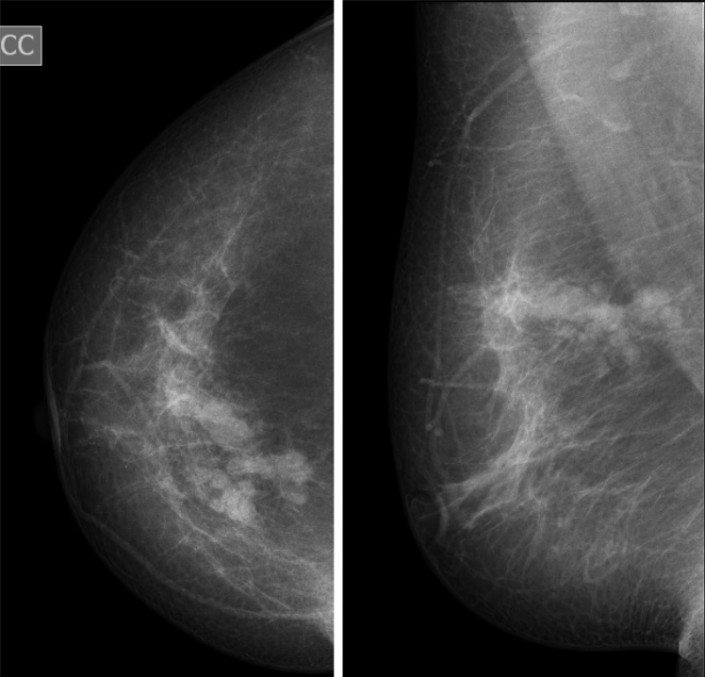

"Первый конкурирующий диагноз, который выставляется пациенткам, - это рак молочной железы или объемное образование, BI-RADS 4", - пишут исследователи.

В одном из случаев 29-летняя женщина обратилась в поликлинику по месту жительства с жалобами на объемное образование в правой молочной железе. Направлена на обследование - маммографию и УЗИ молочных желез. Выставлено подозрение на рак молочной железы. Но после обследования маммолога клеток опухолей не нашли. Отмечается, что пациентка длительное время состояла на учете по поводу эхинококкоза печени и за полгода до событий была оперирована по месту жительства по поводу эхинококкоза печени. Пациентка направлена в Казахский научно-исследовательский институт онкологии и радиологии (КазНИИОиР) для дальнейшего обследования, где и выявили наличие паразитов в груди. Было рекомендовано оперативное лечение.

Как пишут авторы исследования, выявить эхинококкоз в груди помогла информация о наличии этого заболевания ранее. В обоих же случаях болезнь "скрывалась" под видом рака молочной железы. При этом на маммограммах патология не укладывалась в классическую картину патологических состояний (рак, киста, фиброаденома, филлоидная опухоль). Также врачи отмечают, что в обоих случаях образования были безболезненными при пальпации.